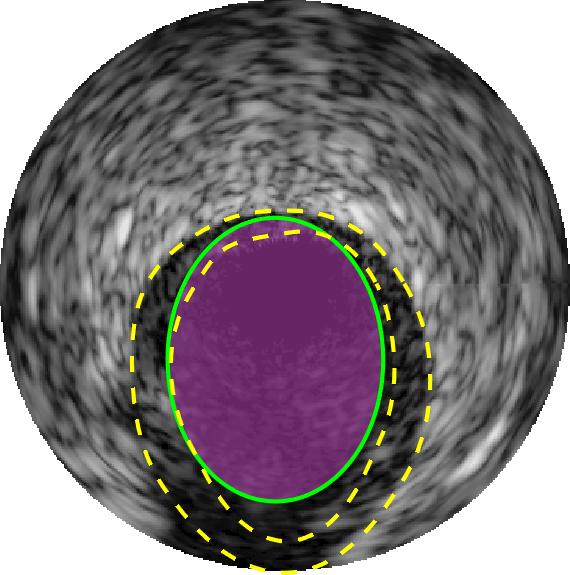

Qualitative evaluations are illustrated in Figure 4 and show the successful segmentation results of the proposed EREL selection strategy for 20 IVUS frames. The lumen areas are highlighted by the magenta colour while the media regions are green. Also, the manually annotated contours for both lumen and media are drawn as yellow dashed lines. As we can see, the chosen frames contain a variety of lumen and media morphologies.